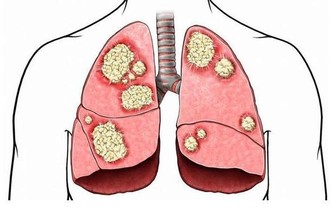

“一口兩口三口”,起初你並沒有發現什麼異常,但時間久了,寄生蟲吃的越來越多,胃受到的傷害越來越大,然後你就感到“胃疼”。往往感到胃疼的時候,胃已經千孔百瘡。而這個寄生蟲就是“幽門桿菌”。

幽門螺旋桿菌是目前發現在人胃中生存的唯一微生物,它的感染率高達50%至60% ,侵蝕胃粘膜,降低胃自我修復功能,有更多患有胃病的人出現。感染幽門螺旋桿菌患者,會出現以下典型的不適症狀!

幽門桿菌是寄宿在胃裡的微生物,肉眼看不到,如果有條件去檢查,

在顯微鏡下,就能看到密密麻麻的幽門桿菌,甚是是可怕。